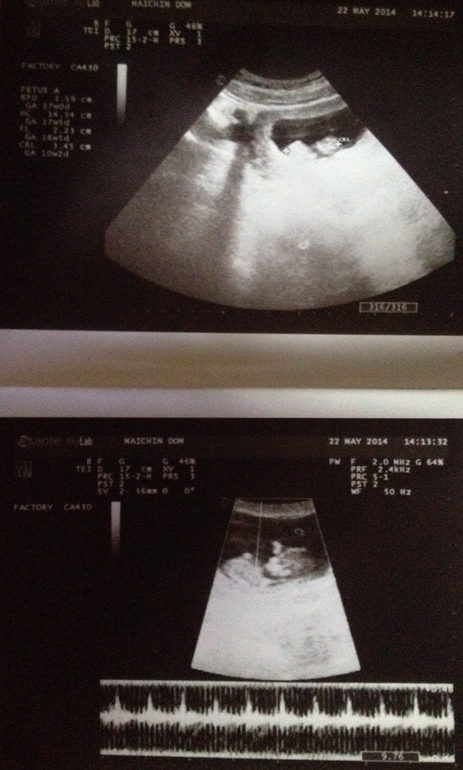

Сходили с мужем на УЗИ :)

Вот, у нас первая фотка есть ^___^ Честно, я пока слабо осознаю, что у нас будет ребёнок, муж, наверное, тоже. Послушали сердцебиение, нам сказали, что всё хорошо. Малявка на УЗИ махала ручкой, классно :)

знаете, мне кажется это и был первый скрининг — кровь + УЗИ. Просто у нас тут все очень спокойные и лишний раз не тревожат :) Врач сказала, что по УЗИ всё хорошо, а анализов надо подождать. В конце июня будет 16 неделя и это видимо будет второй скрининг.

Здравствуйте! Я наблюдалась в Майчин Дом полностью всю беременность, платила типа абонемент. Сколько у них стоит отдельно сделать, увы не знаю. Наблюдалась у Доктора Станевой, она говорит и понимает по русски. Это считается довольно дорогая клиника, наверное, есть варианты и побюджетней :) Но туда много русских приходит рожать и наблюдаться, поэтому обычно нет проблем с языком.